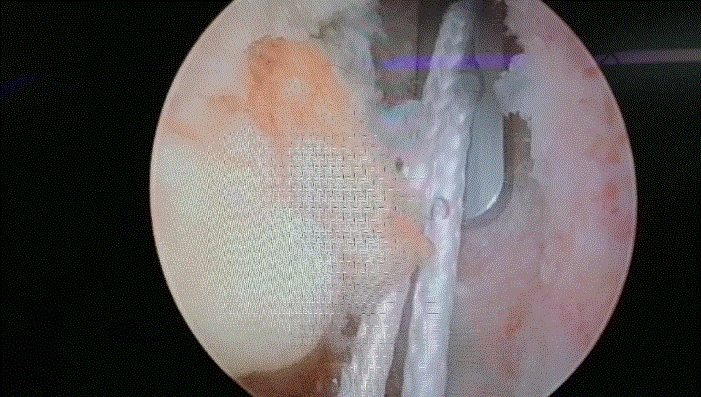

经过 2-4 周的「康复前」活动,等到患膝肿胀消退,我们再根据实际情况,决定是否手术。理论上手术是没有年龄界限的,尽管 55 岁以上的患者很少接受 ACL 重建,但决定是否手术取决于患者病情,包括膝关节不稳定、活动水平等。

术后支具固定,严格按照康复要求,给予功能锻炼。相信半年后,这些年轻人,又可以重拾信心,重返赛场。